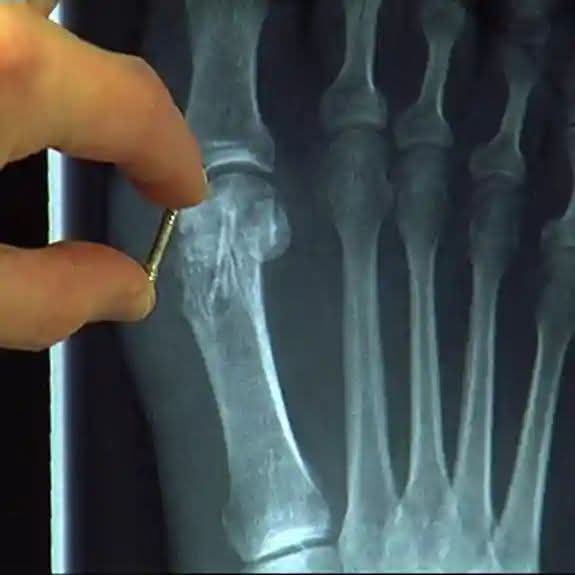

في تطور طبي بارز، نجح باحثو جامعة سامارا الطبية الحكومية الروسية التابعة لوزارة الصحة في تصميم براغي جراحية مبتكرة لتثبيت الكسور العظمية المعقدة، تتميز بقدرتها على التحلل الحيوي الكامل داخل الجسم.

وأوضحت البروفيسورة لاريسا فوليفوي، مديرة معهد بحوث التكنولوجيا الحيوية في الجامعة، أن هذه البراغي – على عكس مسامير التيتانيوم التقليدية التي تستلزم عملية جراحية ثانية لإزالتها – تذوب تدريجياً مع الوقت، ليحل محلها نسيج العظم الطبيعي للمريض دون أي تدخل إضافي.

ويُستخدم الابتكار في عمليات تثبيت العظام، وهي إجراءات جراحية لربط شظايا العظام، ضمن مجالات جراحة الإصابات، وجراحة العظام، وجراحة الوجه والفكين.